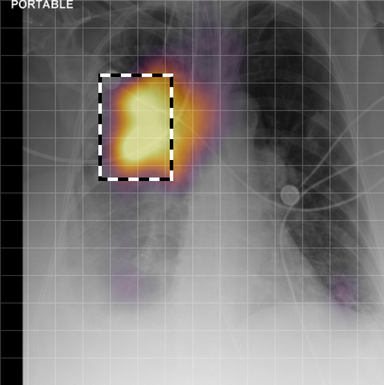

| (1) |

for , where denotes 2D sinusoidal positional encodings [12] and is its temporal counterpart, which is learnt (Fig. 2) [4]. The layer-normalised () [6] output of the final transformer encoder block is an ‘aggregated’ representation of patch-level progression information anchored on the current image. Figure 3 shows attention roll-out [1] applied to after pre-training, showing how the prior image contributes to the fused representation. Figure A.5 further highlights the robustness to variations in pose underlining that registration is not necessary for this encoder.

A.3 Self-attention visualisation

In Figure A.3, we show examples of self-attention rollout [1] maps for pleural effusion and consolidation, including radiologist-annotated bounding boxes surrounding the corresponding pathology in each prior and current image.

To model the attention flow through the transformer encoder block, we first average each attention weight matrix across all heads, subsequently we multiply the matrices between every two layers. For every block we add the identity matrix in order to model the residual connections. Last, we only keep the top 10 of attention weights per block to reduce noise in the final rollout map. In contrast to [21], we do not visualize the rollout map with respect to a [CLS] token. Instead, we choose a reference image patch from the center of the radiologist-annotated bounding boxes, marked with in Figure A.3.

We find that the rollout maps in Figure A.3 are in good agreement with radiologist-annotated bounding boxes, i.e., the reference patch attends to other patches within the bounding boxes in the prior and current image. In addition, we find that BioViL-T is robust to pose variations, e.g., in Figure A.3 (a) we show that despite the vertical shift between prior and current image, the reference patch attends to the correct image patches in the prior image.